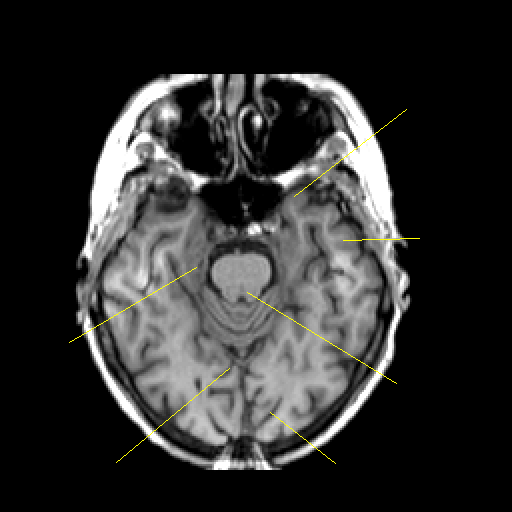

T1-weighted structural MR: Slice 18

Slice 18

Pointers

Labeled